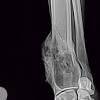

Also known as osteosarcoma, bone cancer is a common diagnosis in felines. Many signs of bone cancer are subtle. Many cancer symptoms in cats are subtle and can be caused by another condition, but if you notice any of the following potential. Chondrosarcoma of the bone is a fast spreading form of bone cancer, which can be life threatening if not diagnosed and treated early. However, cats can still get skin cancer.

Malignant bone cancer in cats is anything but common, but it still has an incidence of about 5 cases per 100,000 individuals. Chondrosarcoma of the bone in cats chondrosarcoma (csa) is a type of cancer that affects the cartilage of the body; And who can blame them? However, there are instances when blood tests can help us diagnose cancer and also help us provide you with the most information about your dog's or cat's condition. As with humans, male cats can develop mammary cancer. Male cats can get breast cancer, too. Occasionally, cats will exhibit a mass growth on their body or a painful inflammation around the sight of the tumor. Cat cancer symptoms can be subtle and cats are good at If you find unexplained lameness in your cat, then it's a very common sign of bone cancer. They are somewhat rare in cats. Lymphoma, squamous cell carcinoma, mast cell tumor, and bone cancer are all common in cats. There are three main forms of bone cancer, but the most common and aggressive is osteosarcoma, which accounts for up to 95% of all cancer diagnoses. Other signs of cancer in cats :

Other types of bone cancer are chondrosarcoma, fibrosarcoma, and hemangiosarcoma. Osteosarcoma, a tumor that affects the bones in your cat's legs, is one of the most frequently occurring cat cancers. Stage 2 is bony damage. While a cancer diagnosis is emotionally devastating, some cancers are treatable if caught early. Many cancer symptoms in cats are subtle and can be caused by another condition, but if you notice any of the following potential. It is the most common malignant cancer diagnosed in cats and dogs today. However, a traumatic injury like a broken bone can lead to cancer, even years after the injury occurred. Cancer cells that spread from tumors in other parts of the body can form two main types of bone tumors: Limbs (upper arm and upper leg bones) pelvis (hipbones) rib cage. If the cancer spreads to the lungs, your cat may also experience breathing problems. Staging is of great value in deciding how to treat the patient. Even if two cats have the same type of cancer, it could affect one more drastically than the other for reasons even doctors can't fully understand or predict. And who can blame them?